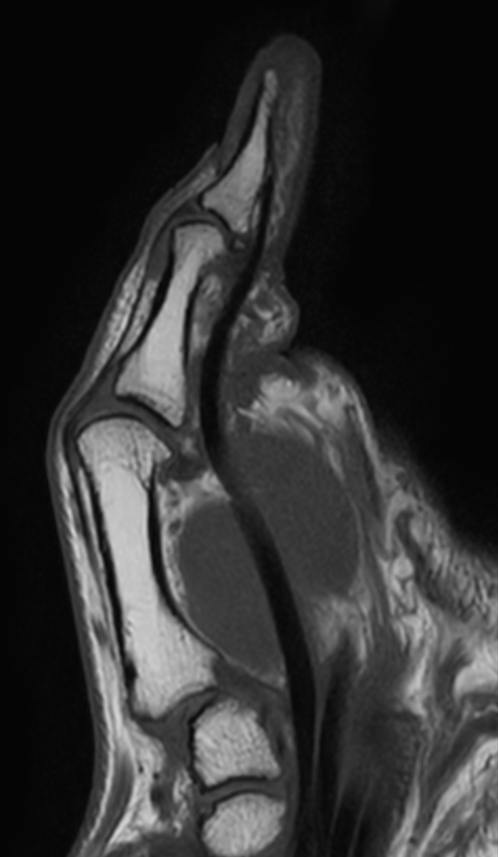

Patient with pathology on the thumb. ExamCard includes mDIXON XD TSE to achieve uniform, complete and consistent fat-free imaging. It simplifies the scan procedure by providing multiple image types in one single scan, including with/without fat suppression contrasts.

PDw TSE mDIXON XD (Water only)